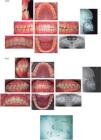

The maxillofacial surgeon instructed the patient to obtain full digital records (panoramic X-Rays, lateral headfi lm and intra and extra oral photographs) before the surgery (Figure 8).

Four days prior to the surgery, the soft tissue analysis (Bell), surgical prediction (5 mm maxillary advancement and 3 mm mandibular retrusion), models surgery and the elaboration of the two surgical splints (intermediate and fi nal) were all performed in conjunction with the maxillofacial surgeon.

After 16 months the orthognathic surgery was performed in which a 5mm maxillary advancement was made and a mandibular retrusion of 3mm (Figure 9). The patient was told to use intermaxillary elastics (1/8”, 3.5 oz squirrel), to overcome the muscular forces.

One month after the surgery, the patient attended the clinic of orthodontics, where the surgical arches were withdrawn and coaxial 0.019” × 0.025” stainless steel arch wires were placed, still with intermaxillary elastics in the posterior area to assist in the settlement of the occlusion. A panoramic X-Ray was indicated to evaluate root parallelism (Figure 10).

After three months 0.017” × 0.025” stainless steel arch wires were placed in both arches, cinched, and crossed intermaxillary elastics (1/8”, 3.5 oz) were indicated on the left side, to improve the posterior occlusion. Final panoramic radiograph and lateral heafilm were obtained (Figure 11).

After 22 months of treatment and once the objectives were achieved, it was decided to remove the appliances. The patient was referred to the periodontist for prophylaxis and the retention stage started with a 3-3 lower fixed retainer and a removable circumferential retainer in the upper arch to help close the remaining spaces of the bands (Figure 12).

RESULTSA skeletal class I was obtained along with a canine class I and a molar class II, favorable inclinations of the upper and lower incisors, a normal overjet and overbite, midlines centered, straight profile, facial harmony, lips on the same plane, friendly smile, and an adequate masticatory function (Figure 13), as well as important changes in the cephalometric values (Table III).